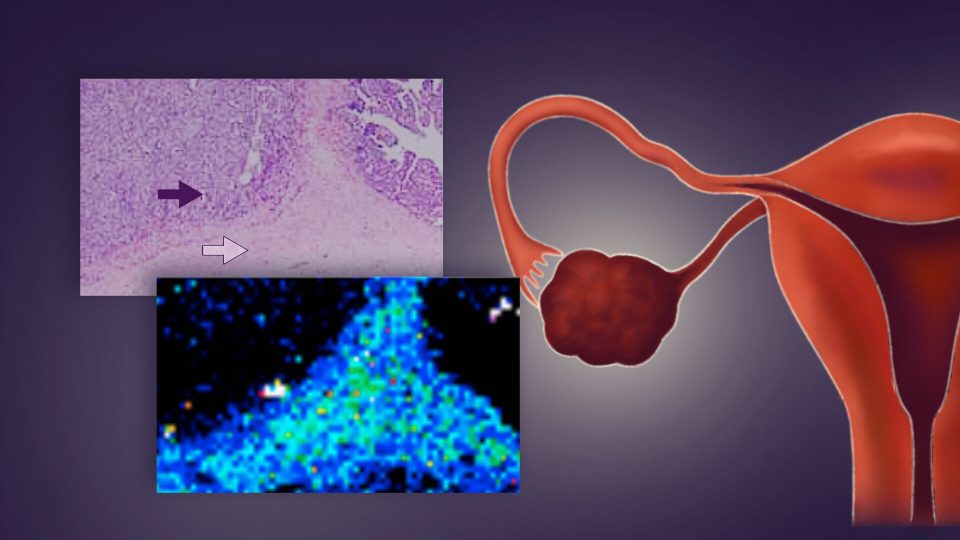

The team looked at the amount of platinum in both the tumor itself and in its stroma, which is the part of the tumor that supplies cancer cells with nutrition and gets rid of waste products. They found that there were two basic types of platinum distribution: one where the platinum was evenly distributed throughout both the tumor itself and the stroma, and one where the platinum was mostly in the stroma.

The difference was staggering: only one of the 11 patients with an even distribution of platinum died in the three years after diagnosis, whereas half of 16 patients with most of the platinum in the stroma were dead within three years. In addition, the patients with tumors that showed an even distribution of platinum were also less likely to develop a tumor that was resistant to further treatment.

“We showed that there were two different patterns of platinum distribution within the tumor tissue. The difference in the distribution was shown to be significantly correlated with prognosis, suggesting that it is possible to discriminate between platinum-resistant and platinum-sensitive tumors before they recur,” explains Kajiyama. “Using this method, early diagnosis of platinum resistance and selection of appropriate postoperative anticancer therapy for patients as well as a new ovarian cancer treatment strategy are possibilities.”